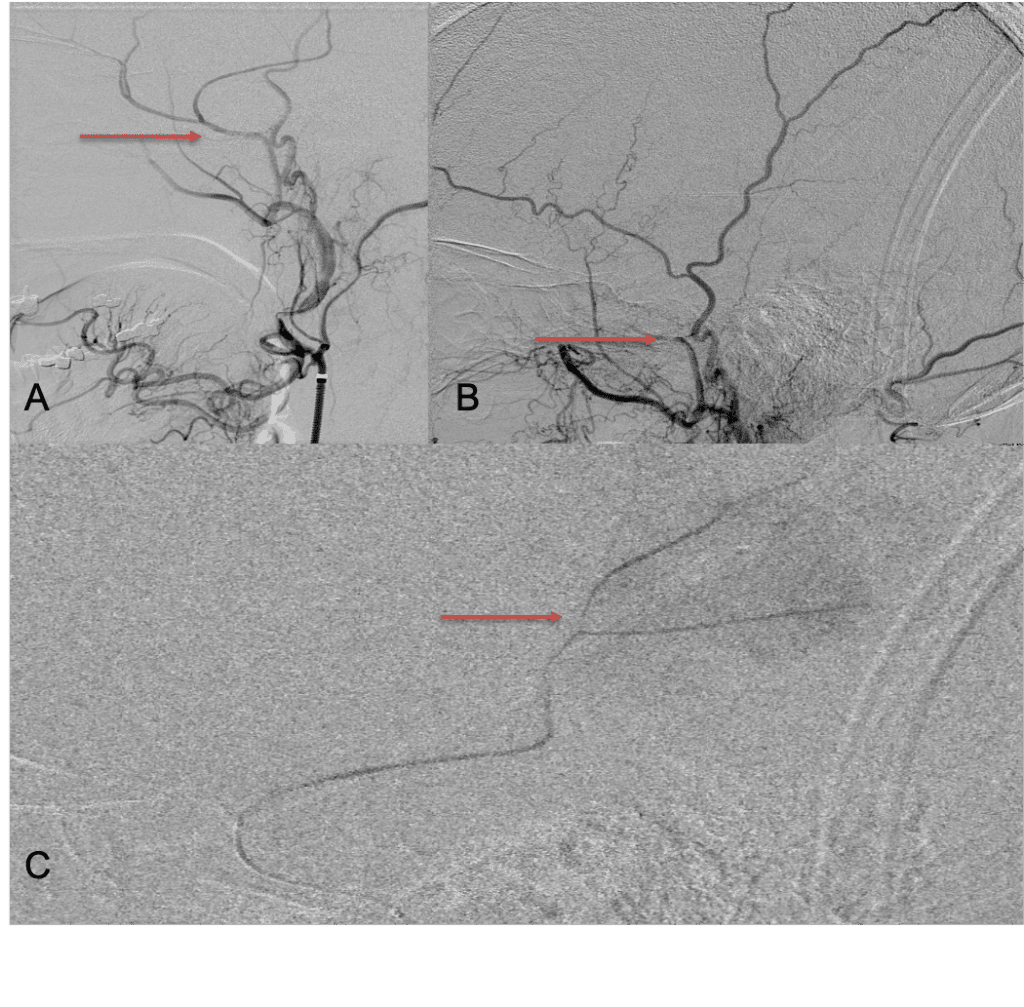

The patient agreed to receive minimally invasive treatment with Bilateral Middle Meningeal Artery Embolization, a new approach to promote resorption of chronic and subacute subdural hematomas in patients that are not improving with conservative measures or have contra-indications to surgical evacuation. Selective catheterization of the Middle Meningeal Artery is followed by transarterial embolization of the territory and inflammatory membranes that are felt to be secreting serosanguinous proteinaceous exceeding the capacity for resorption. MMA embolization was performed bilaterally in this patient. (Figure 2. A and B)

Figure 2. A) Initial right ECA angiogram ; B) Post MMA Embolization; C) Selective Embolization Of Middle Meningeal Artery Membranes using PVA particles (arrows).

Although conventional surgical methods, such as burr hole irrigation or observation in asymptomatic or minimally symptomatic patients have been the mainstay of treatment, middle meningeal artery (MMA) embolization has emerged as a promising adjunctive or alternative treatment. MMA embolization is a neuroendovascular technique which involves placing a microcatheter into the Middle Meningeal Artery, most commonly on the side of the cSDH (occasionally, bilateral embolization has been recommended for larger or bilateral collection. Embolization of both the anterior (frontal) and posterior (parietal) division is performed using a variety of embolic materials (liquid NBCA, Onyx, coils), although polyvinyl alcohol particles of <250 microns are most commonly used to achieve distal penetration and occlusion of the pre-capillary and capillary beds. The micro-leakage of blood and transudative proteinaceous inflammatory fluid in these inflammatory membranes is creating an imbalance in cycle of resorption and preventing resolution or promoting recurrence or growth of these cSDH collections and associated mass effect and midline shift.

Care must be taken to place the microcatheter within a safe position for embolization, with special attention to potential collateral branches to the orbit/eye via sphenoid or meningo-lacrimal branches (which may cause vision loss) or petrosal branches supplying the geniculate ganglion, the tympanic portion of the facial nerve, and often the trigeminal nerve via a branch coursing along the greater petrosal nerve. Once a safe position in the main trunk of the MMA, or superselectively in each of its divisions is achieved, embolization is performed until stasis of contrast and dense contrast staining of the dura is observed within the embolized vascular beds.7

Masaki Komiyama first introduced MMA embolization as a treatment option for recurrent cSDH in 1994, when he described employing it in combination with burr hole drainage in a traumatic patient with a linear skull fracture and recurrent hemorrhage (3). Over the last decade, there has been renewed interest in endovascular approaches to treating cSDH, secondary to the significant rate of recurrence, persistence, and complications associated with surgical only approaches. In the most recent and largest meta-analysis performed by Ironside etal., they reviewed a total of 20 studies comprising 1416 patients with cSDH, who met their inclusion criteria. Five double-arm studies (902 patients) compared outcomes with conventional management versus MMA embolization. Fifteen single-arm studies (514 patients) reported outcomes with or without surgical evacuation. In this review, MMA embolization was performed for recurrent cSDH after prior surgical evacuation in 47.8%, prophylactically after surgical evacuation in 23.2%, and primarily(upfront) in 28.4%. Embolization materials included particles (n=403), liquid embolics (n=143), coils (n=171), microspheres (n=86), and Onyx (n=80). The pooled recurrence rates (MMA vs conventional) were 4.8% (95% CI 3.2% to 6.5%) vs. 21.5%(0.6% to 42.4%), the surgical rescue rates, 4.4% (2.8% to 5.9%), vs 16.4% (5.9% to 27.0%), and in-hospital complication rates 1.7% (0.8% to 2.6%), vs 4.9% (2.8% to 7.1%). Compared with conventional management, MMA embolization was associated with lower rates of cSDH recurrence (OR=0.15 (95% CI 0.03 to 0.75), p=0.02) and surgical rescue (OR=0.21 (0.07 to 0.58), p=0.003). In-hospital complication rates were comparable between the two cohorts (OR=0.78 (0.34 to 1.76), p=0.55).